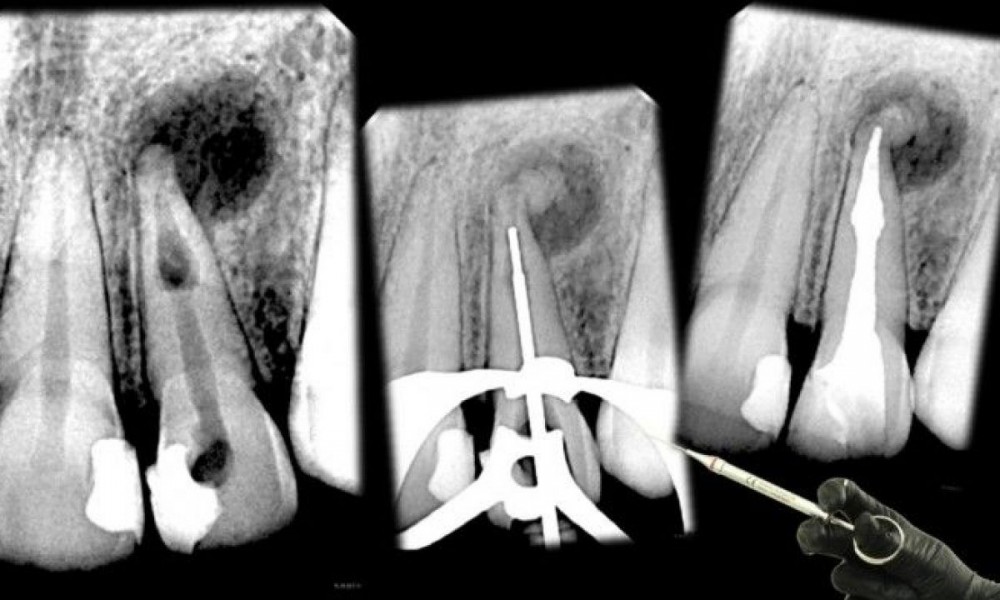

Early detection is key because Dental Internal Resorption can progress silently, sometimes showing no visible symptoms until significant damage has occurred. Regular dental check-ups and imaging tests, such as X-rays, are vital for identifying the condition before it becomes severe.

Dental professionals rely on diagnostic tools like dental X-rays and cone beam computed tomography (CBCT) scans to identify the extent of resorption. These imaging techniques help differentiate Dental Internal Resorption from other dental conditions and guide treatment decisions.